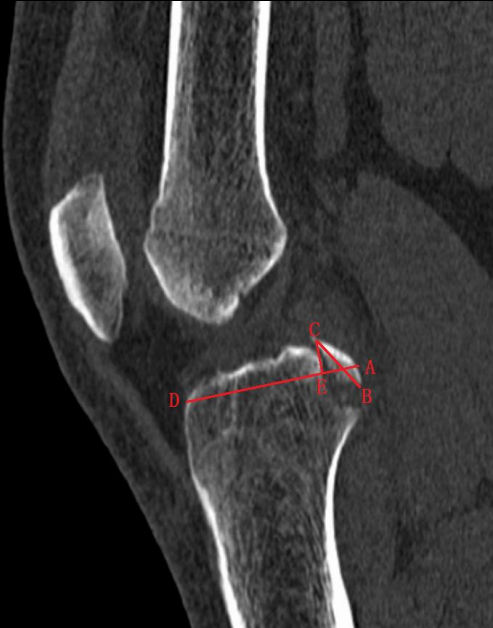

总结我科临床资料,提出后交叉韧带止点撕脱骨折分型,并据分型设计

相应术式选择!依据:

1.CT与MRI矢状位骨折块长度(BC);

2.矢状位撕脱骨折前后距与胫骨平台前后距比例(AE/AD);

Ⅰ型:撕脱骨折块BC小于15mm,AE/AD小于1/2;

Ⅱ型:撕脱骨折块BC大于/等于15mm,AE/AD小于1/2,常见;

Ⅲ型:撕脱骨折块BC大于15mm,AE/AD大于或等于1/2;

ⅢA型:多块撕脱骨折块,BC大于15mm,AE/AD大于1/2;

ⅢB型:骨折块合并半月板撕裂,BC大于15mm,AE/AD大于或等于

1/2。

ⅢC型:髁间棘陈旧性撕脱骨折, BC大于15mm,AE/AD大于或等于